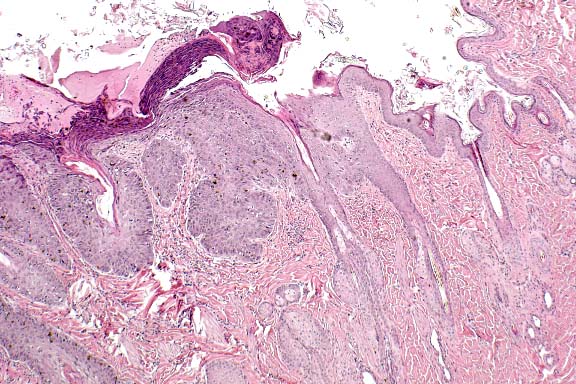

Case 29-2. Skin. Junction between normal skin and squamous cell carcinoma that has not broken through the basement membrane (in situ). Some sloughing superficial necrotic debris is on the surface. 4X

AFIP Diagnosis: Haired skin: Squamous cell carcinoma in situ, Domestic Shorthair, feline.

Contributor's Diagnosis and Comments: Squamous cell carcinoma in situ (Bowen's disease).

Squamous cell carcinoma (SCC) in situ is considered to be a premalignant condition. In humans, SCC in situ has been associated with an internal malignancy or arsenic exposure. This form of squamous cell carcinoma does not require ultraviolet light exposure and a sparsely haired/poorly pigmented skin for its development, as is seen in most cases of SCC in the cat which has a predilection for eyelids, ears and planum nasale. We do not know if there is any relationship between the presence of the mediastinal thymoma and hepatoma and the development of these lesions.

SCC in situ has been associated with papillomavirus infection in the cat. The virus has been demonstrated by immunohistochemical methods in the lesions. No evidence of virus was detected on histopathology, but immunohistochemistry was not undertaken.

SCC in situ is considered to be rare in cats and very rare in dogs.2 Clinically, affected animals present with one or more erythematous, pigmented, nodular plaques which may be eroded or ulcerated. The plaques are well demarcated from the surrounding haired skin. Lesions may occasionally show local invasion or microinvasion, but metastasis has not been reported. Older cats are most often affected, and there is no known breed predilection.

SCC in situ is distinguished from actinic keratosis primarily on clinical grounds, i.e. actinic keratosis affects only sun-exposed, lightly pigmented skin. A histologic feature of actinic keratosis which is not seen in this case is fragmentation and replication of elastin fibers.